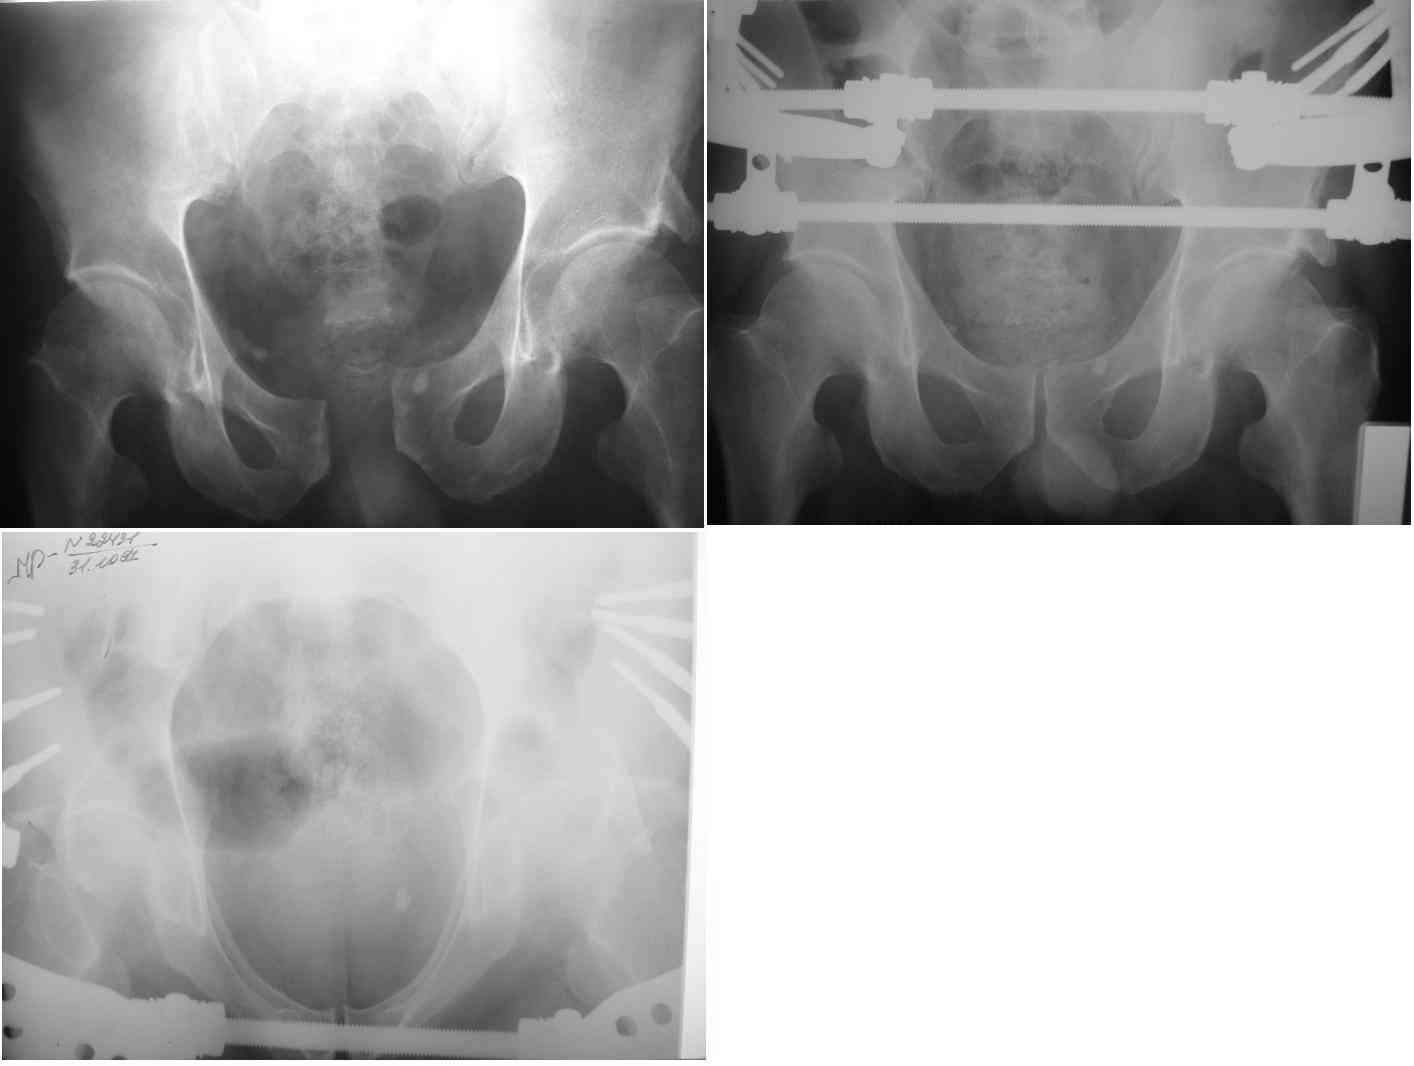

ПЕРЕСМАТРИВАЛ РАЗНЫЕ СНИМКИ И НАШЕЛ НА ЭТУ ТЕМУ ФОРУМА СНИМОК. БОЛЬНОЙ БЫЛ ПРООПЕРИРОВАН НА ПРАВОЕ БЕДРО ПОСЛЕ ЧЕГО СДЕЛАН ТАЗ В ЦЕЛОМ. ВОТ ЧТО НАШЛОСЬ.

КАКОЕ ВАШЕ МНЕНИЕ О ТАКТИКЕ.

ДУМАЮ ПРОШЛО ОКОЛО 10 ДНЕЙ.

Вот вариант решения похожей ситуации

Алексей Смирнов,

Нижний Новгород